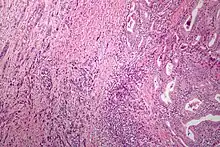

Microscopic image of anaplastic thyroid carcinoma. H&E stain. | |

Anaplastic tumors have a high mitotic rate and frequently invades the local blood and lymphatic vessels.[5] Cellular death is frequently visualized on microscopic images.[2] The presence of regionally swollen lymph nodes in older patients in whom needle aspiration biopsy reveals characteristic vesicular appearance of the nuclei supports a diagnosis of anaplastic carcinoma. Microscopic images of ATC usually show inflammatory cells from the immune system such as T cells and macrophages.[2]